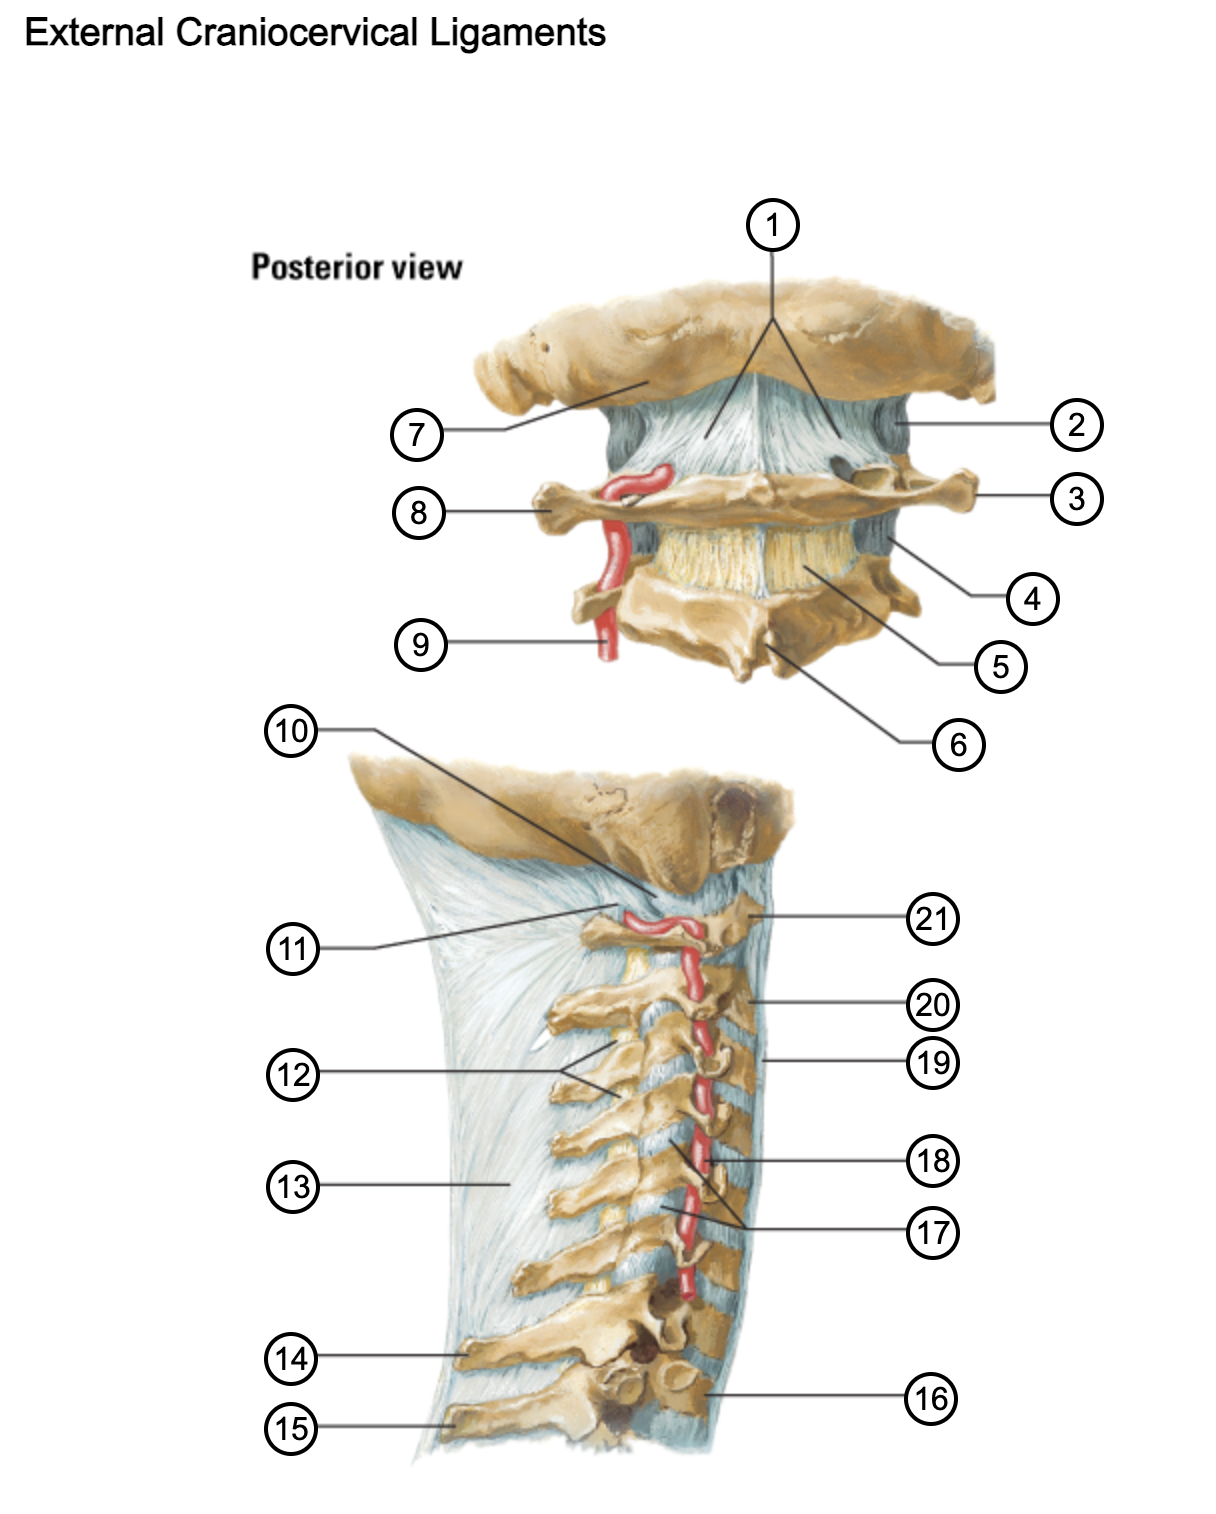

1

posterior antlantooccipital membrane

2

capsule of atlantooccipital joint

3

transverse process of atlas (C1)

4

capsule of lateral atlantoaxial joint

5

ligamenta flava

6

spinous process

7

occipital bone

8

transverse process of atlas (C1)

9

vertebral artery

10

capsule of atlantooccipital membrane

11

posterior atlantooccipital membrane

12

ligamenta flava

13

nuchal ligament

14

spinous process of C7 vertebra

15

spinous process of T1 vertebra

16

T1 vertebra

17

zygapophysical joints (C4-5 and C5-6)

18

vertebral artery

19

anterior longitudinal ligament

20

body of axis

21

Atlas (C1)